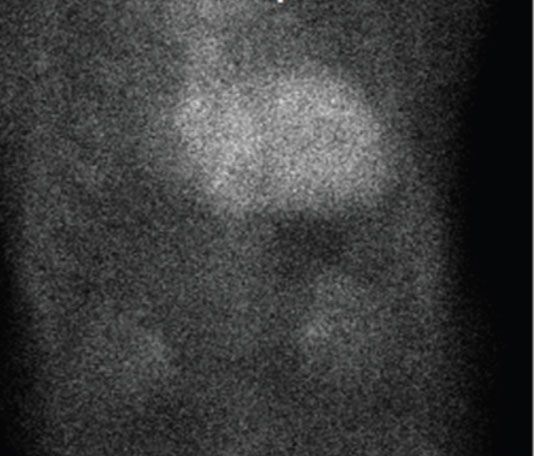

ΤΟ ΤΟΜΟΣΠΙΝΘΗΡΟΓΡΑΦΗΜΑ ΑΙΜΑΤΩΣΕΩΣ ΤΟΥ ΜΥΟΚΑΡΔΙΟΥ

Το σπινθηρογράφημα αιματώσεως του μυοκαρδίου είναι μια μελέτη της αιματώσεως του μυοκαρδίου που γίνεται με την χρήση ραδιενεργού Θαλλίου (Tl-201) ή ραδιοφαρμάκων επισημασμένων με τεχνήτιο (Τc99m) (SESTAMIBI ή TETROFOSMIN). Συνήθως το σπινθηρογράφημα μυοκαρδίου γίνεται συνδυασμένα υπό συνθήκες κοπώσεως και ηρεμίας ή και υπό φαρμακευτική κόπωση. Συχνότερα γίνεται χωρίς συγχρονισμό με το ηλεκτροκαρδιογράφημα (ΗΚΓ) αλλά μπορεί να πραγματοποιηθεί και σε συγχρονισμό με το ΗΚΓ (gated SPECT) οπότε υπολογίζεται και το κλάσμα εξωθήσεως της αριστερής κοιλίας και ελέγχεται η κινητικότητα των τοιχωμάτων της. Το σπινθηρογράφημα μυοκαρδίου μετά δοκιμασία κοπώσεως ή ‘φαρμακευτική κόπωση’ με διπυριδαμόλη είναι η πλέον ευαίσθητη, μη επεμβατική μέθοδος διάγνωσης και εντόπισης της ισχαιμίας του μυοκαρδίου. Έχει σημαντικό ρόλο στην εκτίμηση του κινδύνου ασθενών ύποπτων ή ασθενών με διαγνωσμένη στεφανιαία νόσο, καθώς και στην εκτίμηση της βιωσιμότητας του μυοκαρδίου μετά από έμφραγμα. Τέλος έχει σημαντικό ρολό στην εκτίμηση του κινδύνου προ της εκτέλεσης μεγάλων χειρουργικών επεμβάσεων